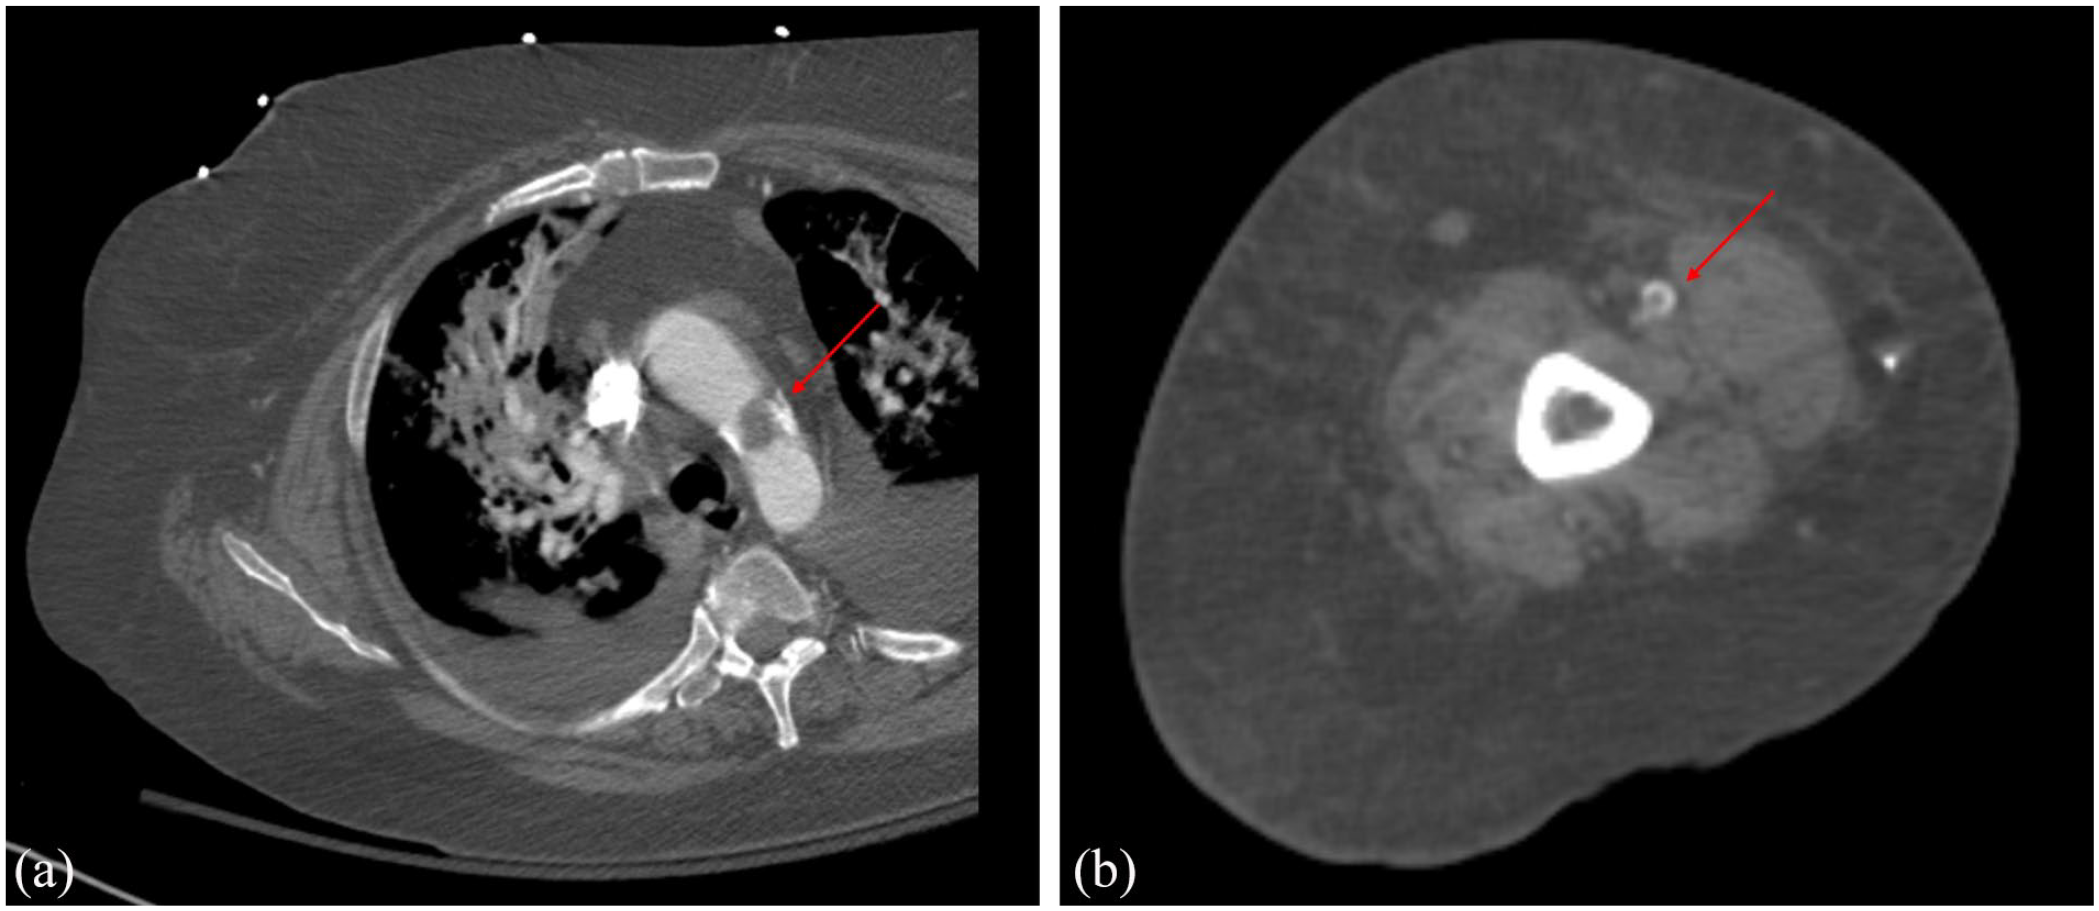

The patient is a 54-year-old white female with a medical history of seropositive RA, positive anticardiolipin IgG and IgM antibodies, and a remote pulmonary embolism treated with apixaban who presented with a 5-day history of left foot swelling, pain, paresthesia, and skin discoloration. A computed tomography (CT) angiogram showed focal stenosis of the left femoral artery. She underwent stenting and a bypass which was complicated by graft occlusion, and she required a subsequent left above-the-knee amputation (AKA). Three days after her left AKA, thrombi in her aortic arch (Figure 1(a)), right brachial artery (Figure 1(b)), right ulnar artery, left subclavian artery, and superior vena cava were discovered despite therapeutic anticoagulation with intravenous heparin.

Representative images from the CT angiography of the chest and the right upper extremity: (a) nonocclusive arterial thrombus within the midportion of the aortic arch and (b) partially occlusive thrombus within the right brachial artery.